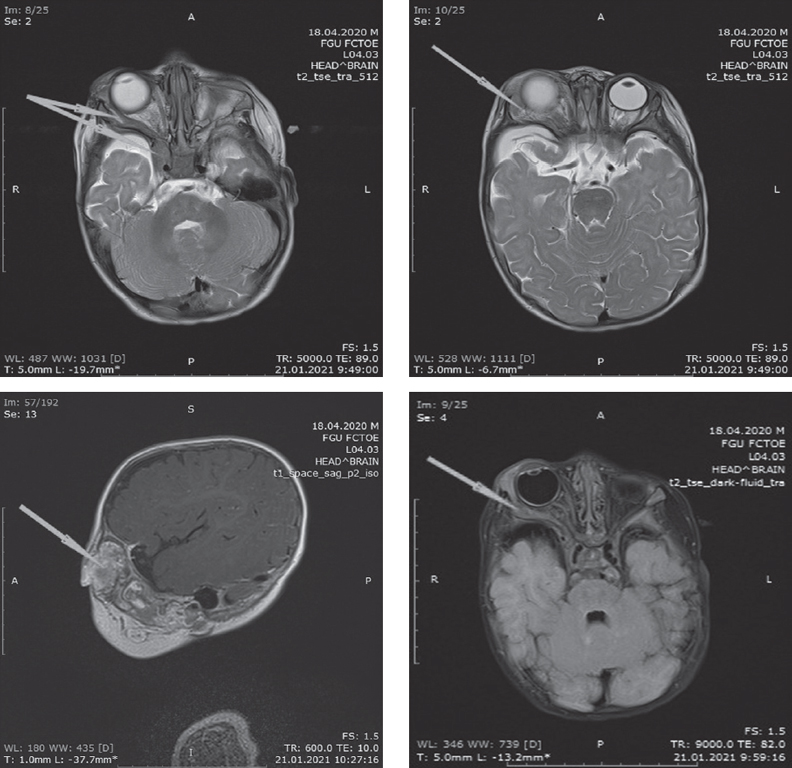

При магнитно-резонансной томографии выявлено объемное образование верхнего века правой орбиты с распространением в переднюю черепную ямку (рис. 2).

Рис. 2. Магнитно-резонансная томограмма пациента. Объемное образование верхнего века правой орбиты с распространением в переднюю черепную ямку (стрелки)

Fig. 2. Magnetic resonance imaging of patient. Volumetric formation of the upper eyelid right orbit with extension into the anterior cranial fossa (arrows)